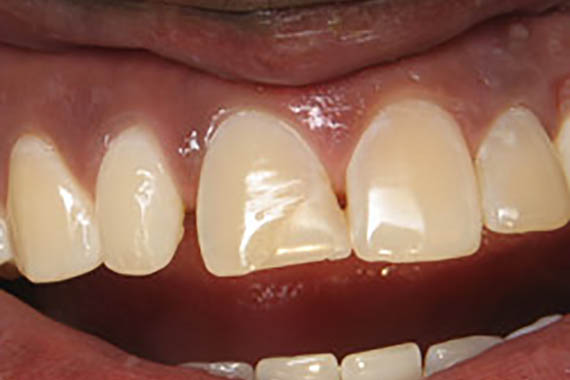

Crowns

Before

After